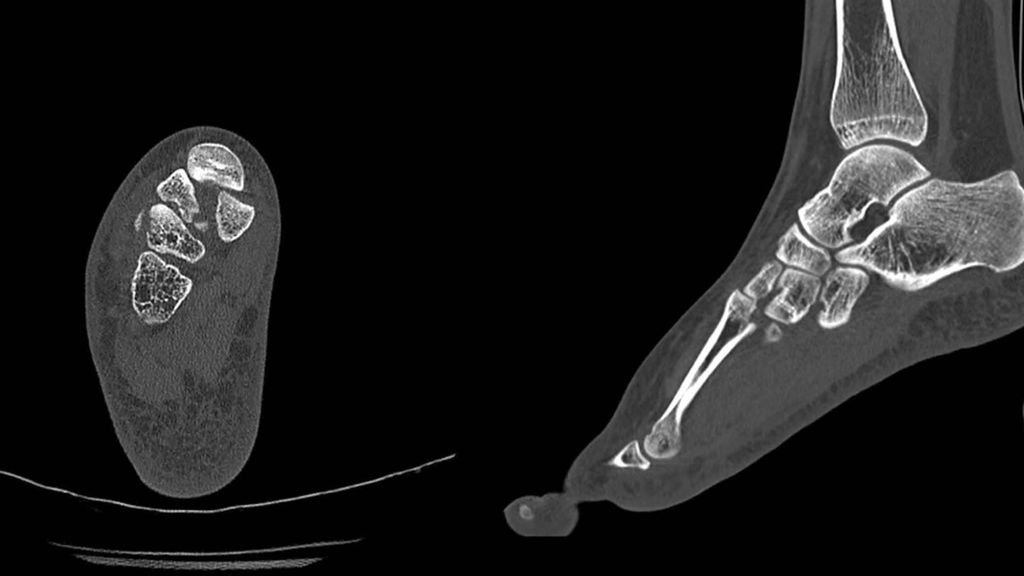

Häufig findet sich in der nativradiologischen Bildgebung kein absolut sicherer Hinweis auf eine Fraktur oder Luxation, da sich die knöchernen Strukturen in der Projektion überlagern. Hier sind entweder gehaltene Röntgenaufnahmen unter Bildwandler oder eine computertomografische Abklärung durchzuführen (Abb. 2).

Abb. 2: CT-verifizierte knöcherne Absprengungen und Subluxation zwischen dem Os cuneiforme mediale und dem metatarsalen Gelenk II des in Abbildung 1 im Nativröntgen dargestellten Fußes

Nun erfolgt die radiologische Überprüfung der Repositionsergebnisse unter Bildwandlerkontrolle, wobei sich unserer Erfahrung nach ein 3D-CT-Bildwandler bewährt hat. Meistens haben sich durch die Repositionsmanöver des I.–III. Tarsometatarsalgelenkes das IV. und V. Tarsometatarsalgelenk spontan mitreponiert; nur bei weiter bestehender Luxation ist eine offene Reposition durch einen zweiten Zugang notwendig. Auch hier werden die Gelenke mit Kirschnerdrähten in der Reposition gehalten. Anschließend erfolgt die temporäre Transfixation der Gelenke.